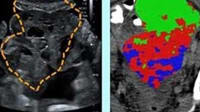

00:02:20 Sybil can classify the image as a high-risk person or a non high-risk person. Then, the doctor is able to make a clinical decision. - The power of Sybil really lies in integrating all that information and not just the information that we as radiologists have sort of defined as relevant over time. - So, this is an example where Sybil really was able to tell the future in a way. This is the same guy two years apart,

00:02:54 and here, the radiologist didn't see a lung cancer. - [Radiologist] As a radiologist, I wouldn't have pointed to this at all. - But Sybil was able to say, something about this scan makes me worried, especially this little area. - In that location. Correct. - And then the same guy, two years later, there's actually, a lung cancer in that area. - Yeah.